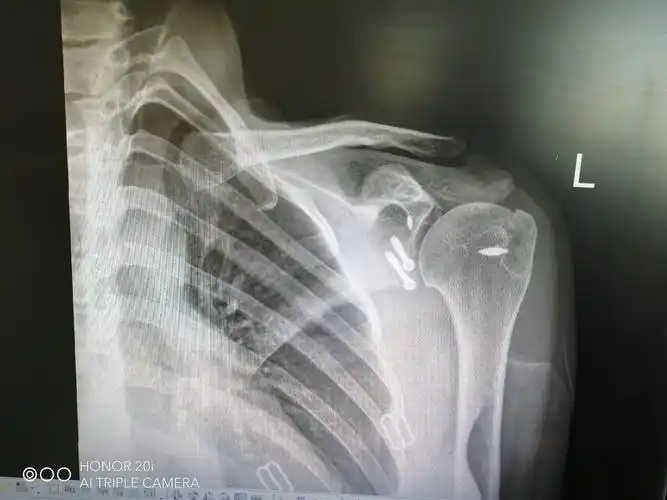

肩峰撞击症肩袖损伤病例

肩胛骨合并锁骨骨折求治疗方案

右肩胛骨锁骨骨折2个月

肩胛盂骨折,肩袖损伤是否需要手术?

一例肩胛骨骨折

肩盂骨折

求助肩胛骨有骨折吗明确诊断